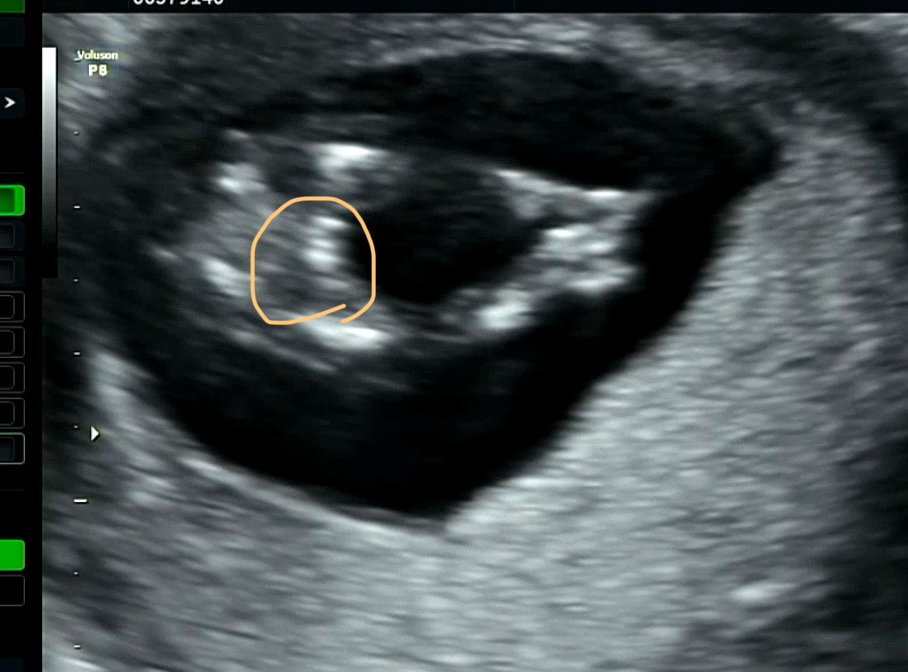

울애기 정밀을 야무지게 들여다봤는데

움직임이 적어서 애를 먹었다.

샘이 초음파기계로 퉁퉁퉁퉁 치면서 깨웠지만 그래도 졸린 아기..

나가서 운동좀 하고 왔다갔다 하고 오라고 하셔서

나가자마자 사탕 한입 먹고, 복도를 돌아다녔다

병정처럼 다리를 올렸다 내렸다하면서 복도 순찰 5바퀴정도 하니

다시 샘이 우리를 불러주셨따!

그래서 다시 초음파~! 다시 다행히 이리저리 움직이는 아기!

각을 잘 잡아서 투명대 검사도 했는데 투명대는 1.67로 3mm 이하 무난하게 통과했다 :)

귀도 생기고 콧대도 생기고..! 콧대는 1mm 이상이면 안정권이라고 하셨다

성별을 봐주신다고 했는데, 가랑이를 딱 보니 동그란 주머니가 안보이는게

이대로 가면 딸램, 반전이 있다면 아들이 될 것이라 하셨다!